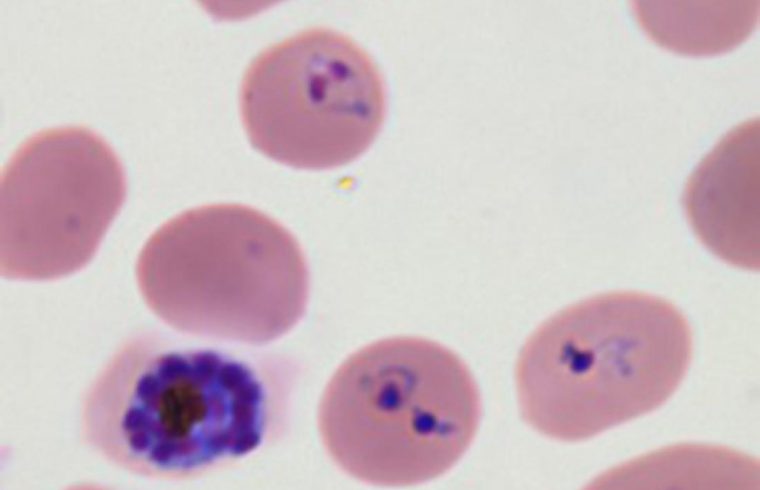

Malaria parasites transform healthy red blood cells into rigid versions of themselves that clump together, hindering the transportation of oxygen. The infectious disease affects more than 200 million people across the world and causes nearly half a million deaths every year, according to the World Health Organization’s 2018 report on malaria. Until now, however, researchers did not have a strong understanding of how the parasite so effectively infiltrated a system’s red blood cells.

The researchers focused on Plasmodium falciparum, the parasite that causes the most severe form of malaria. This parasite infects a host red blood cell, triggering the production of several proteins into the host cell’s cytoplasm—the bulk of the cell’s mechanics and the liquid in which they’re held, ultimately transforming the cell’s physical form. Not only does this transformation make the cells stick in place, out of the body’s immune response, it also helps the parasite travel to the surface of the cell and infect others. Together, the proteins work to proliferate the parasite, leading to the propagation of the malaria parasite.

Previously, it was difficult to understand how the parasite works with the triggered proteins because the parasite was predicted to export about 400 proteins, yet another study found that proteins without the specific genetic sequence could also be exported to the cell’s cytoplasm. In this study, the researchers opted to focus on one of these proteins without the parasitic mark—skeleton-binding protein 1 (SBP1), which is known to be highly important for malaria to propagate. By studying a protein known to be related to malaria virulence, but that isn’t specifically triggered by the parasitic proteins, the researchers could narrow in on specific protein interactions to understand how the infection traffics within and beyond the host cells.

They used highly sensitive mass spectrometry to image the proteins interacting with SBP1 throughout the proliferation process, leading to the identification of several proteins specifically connected to transforming the host cell.